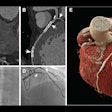

Clinically Meaningful AI Detection of Interval Cancers